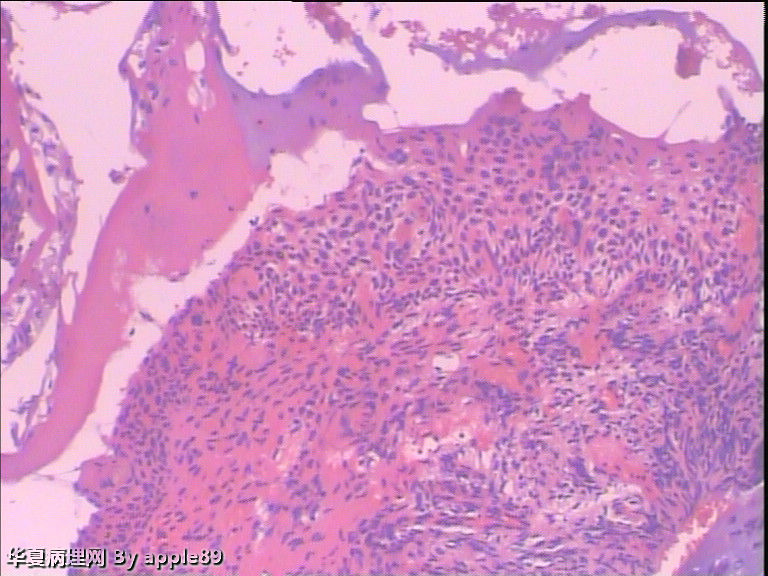

患者女,35岁,因急性粒细胞白血病做化疗,化疗后月经周期紊乱,自今年5月份来月经后就一直月经未来潮,既往月经规律,量正常,无痛经、腹痛等症状。患者育有三胎,已结扎。请妇科会诊,取了宫颈液基。3215

病人做阴道镜,没有看到明显醋酸白区域,随机活检了几块,由于组织受压变形,有点难看,不过补切之后,还是没发现啥问题。前两张是我从阴道镜报告上截的图,后几张是活检图

这个我也报的HSIL,但是活检结果挺郁闷……

这个报告你会怎么发?另外,对于片中的异型细胞你怎么看,难道是化疗后的反应?化疗(具体用药不详)使患者月经失调,会不会也影响宫颈细胞?